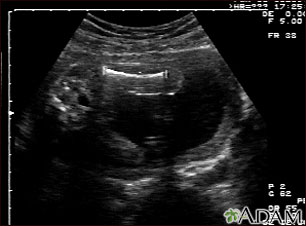

Ultrasound, normal fetus - femur measurement

This is a normal ultrasound of the fetus performed at 19 weeks gestation. A clear view of the left femur (the large bone of the leg) can be seen in the middle, towards the top of the ultrasound screen.